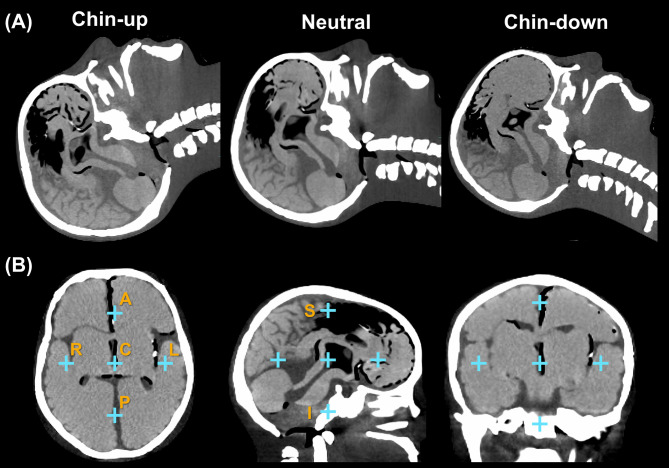

Materials and methods: An anthropomorphic head phantom was used to simulate three head postures, chin-up, neutral, and chin-down, each stabilized with a corresponding thermoplastic mask. Seven isocenter positions were defined: one central position and six offset positions, each 5 cm away in a cardinal direction. Treatment plans incorporated multiple couch angles (0°, 30°, 45°, 60°, and 90°). The Catalyst+ HD system's accuracy was evaluated by comparing its detected displacements to predefined shifts applied using a HexaPOD evo RT system. Translational shifts of ±3 mm and rotational shifts of ±2° were introduced. Statistical analysis was conducted using the Wilcoxon signed-rank test.

Abstract Image